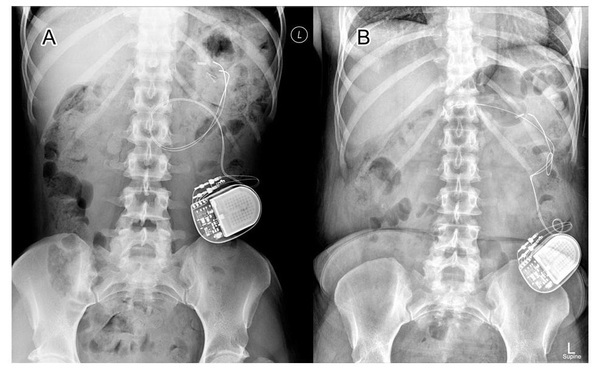

A 47-year-old woman with diabetic gastroparesis for which she had gastric electrical stimulation (GES) implantation 5 years ago returns to clinic for worsening symptoms of nausea, vomiting, and epigastric pain. She has lost 3 kg in the past 3 months. She has been unable to tolerate oral intake for the past week. Stimulator interrogation recently showed normal function. EGD within the last month was unremarkable. Laboratory test results reveal potassium 3.1 mEq/L (normal: 3.5-5.0 mEq/L) and glucose 458 g/dL (normal: fasting 70-100 g/dL). Abdominal x-rays (AXR) showed the results in the figure. What is the next step in management?

• GES devices were approved by the FDA in 2000 for refractory symptoms of gastroparesis of diabetic or idiopathic etiology. Two leads are implanted in the stomach muscle wall to deliver low frequency electrical stimulation. This is believed to affect vagal afferent nerves and decrease symptoms, mainly nausea in diabetic gastroparesis patients. Adverse event rates range from 5-10% and include infection, lead dislodgement, and bowel obstruction. The case demonstrates lead displacement seen in the figure, demonstrating the stimulator overlying the iliac crest with 1 of the 2 leads displaced and migrating into the duodenal bulb, resulting in intermittent gastric outlet obstruction.

• A surgical consult should be obtained to remove the displaced gastric stimulator lead. This case highlights the importance of recognizing complications of GES placement presenting with worsening symptoms of gastroparesis. AXR should be obtained and compared with initial AXR to check for lead displacement.